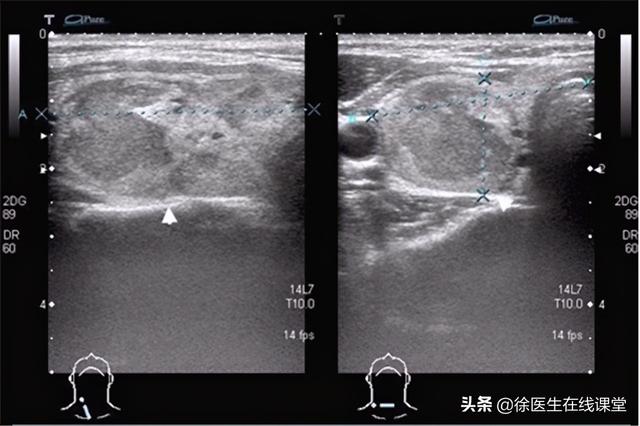

双侧甲状腺多发胶质结节 双侧甲状腺多发胶质结节2类

甲状腺结节的类型较多,比如甲状腺囊肿,它占甲状腺结节的15%~20%,可以说是大多数患者最容易患上的甲状腺结节之一,除此之外是胶质结节,不过这种结节单发性较少,女性的发病率高,在女性年轻以及怀孕的时候,很容易患上这种疾病,有没有哪种类型是单发性甲状腺结节癌变率较高的呢?